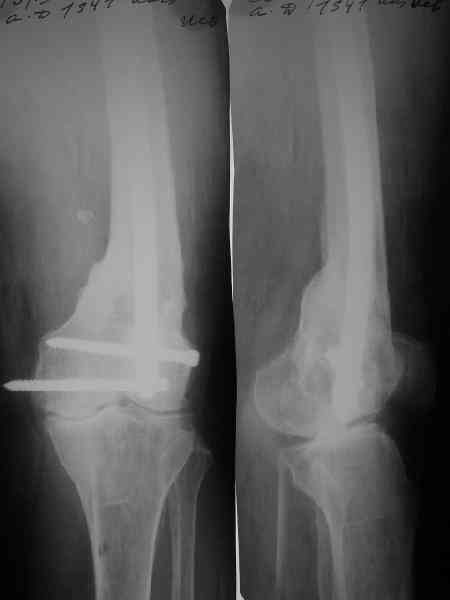

По всей вероятности, после перелома бедренной кости, случившегося 15 лет назад, у больной сформировался псевдоартроз в дистальной эпиметафизарной зоне. Травма этого года привела, с моей точки зрения, к частичному разрушению псевдоартроза, а не к повторному перелому. Учитывая амнестические данные о больной, я бы не спешил с оперативным вмешательством, а предложил бы больной съёмный ортез и нагрузку на ногу в течение двух-трёх месяцев. Такой промежуток времени при данной патологии не ухудшит условия для оперативного вмешательства, если оно потребуется, но позволит более определённо установить необходимость такового, если конечность не станет опорной или больная сама станет настаивать на оперативном вмешательстве.

Что касается самого оперативного лечения, то оно представляет значительные трудности и положительный исход его не столь очевиден. С моей точки зрения, адекватная фиксация любой металлоконструкции в дистальном отломке бедренной кости невозможна. Поэтому вариантов вмешательства два: либо ВКДО с фиксацией голени (что, учитывая конституцию больной и сопутствующую патологию, менее приемлемо), либо антеградный БИОС с прохождением стержня через коленный сустав и дистальным блокированием в проксимальном эпиметафизе большеберцовой кости. И в том и другом случае потребуется открытая репозиция и костная пластика (возможно в несколько этапов). Вопросы восстановления длины конечности и функции коленного сустава на данном этапе лечения не главные. Цель оперативного лечения – восстановление опорной функции конечности и сращение перелома.

Пример подобного ложного сустава в приложении.